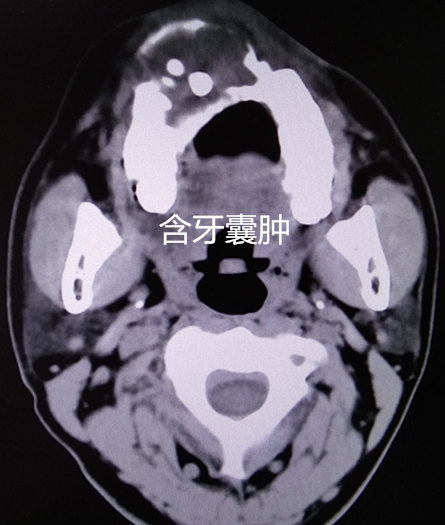

3.侵犯上颌窦的牙源性囊肿多见含牙囊肿,多发于青年,系牙发育异常所引起。治疗以摘除囊肿同时处理病牙。